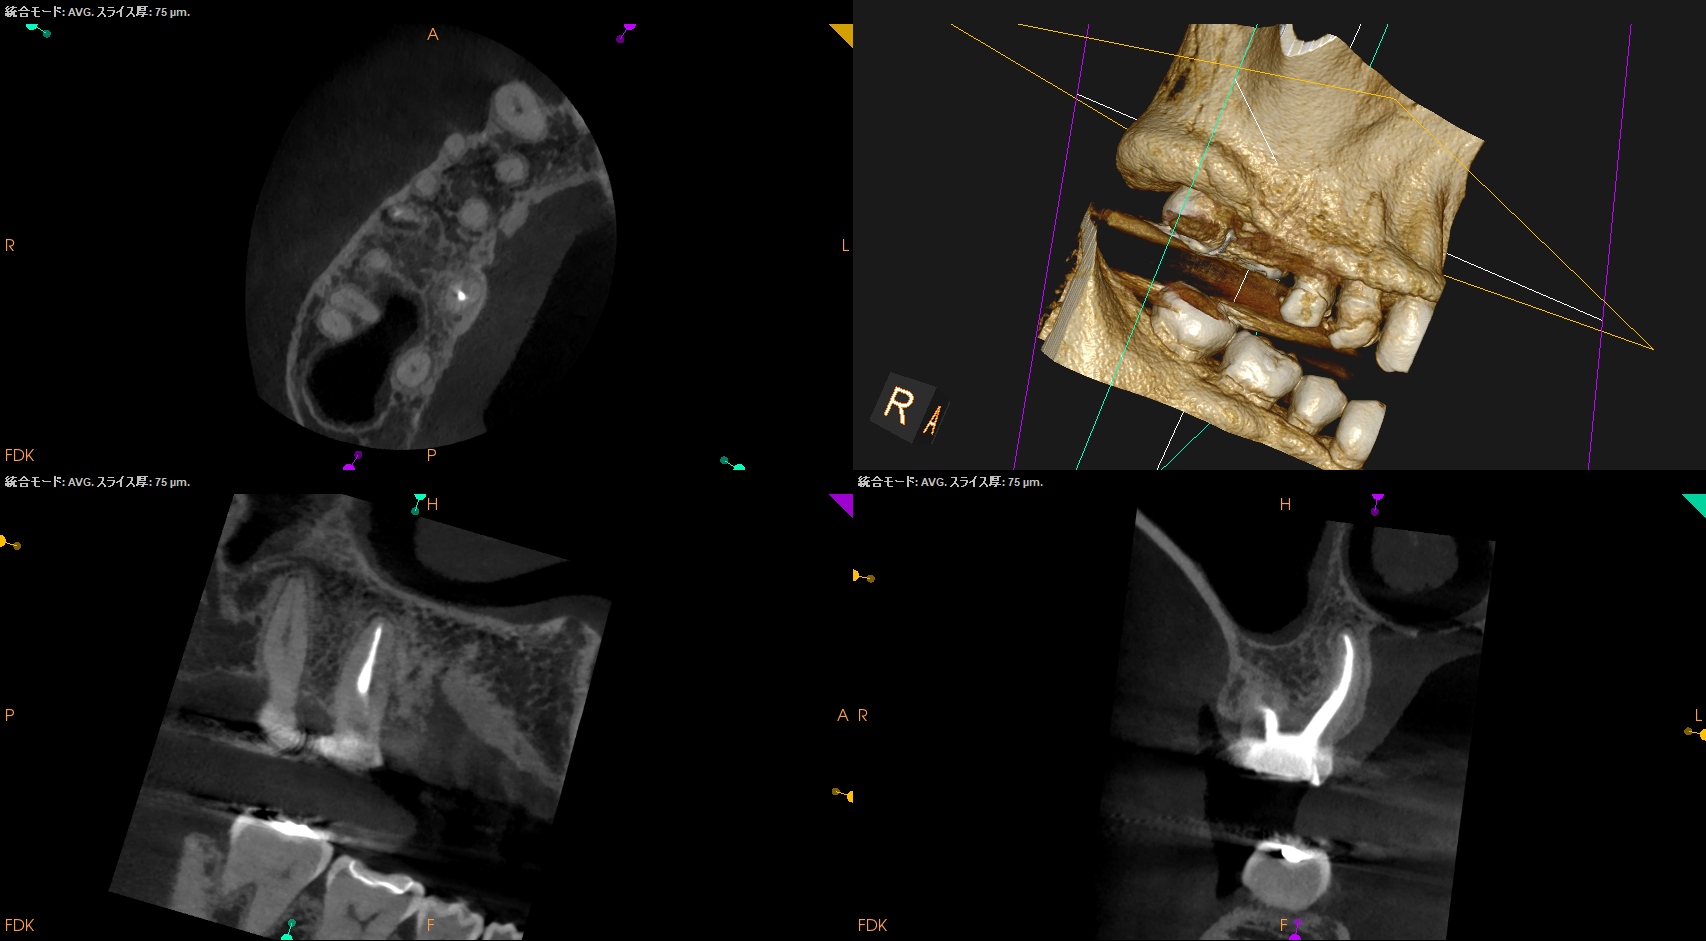

Post-op